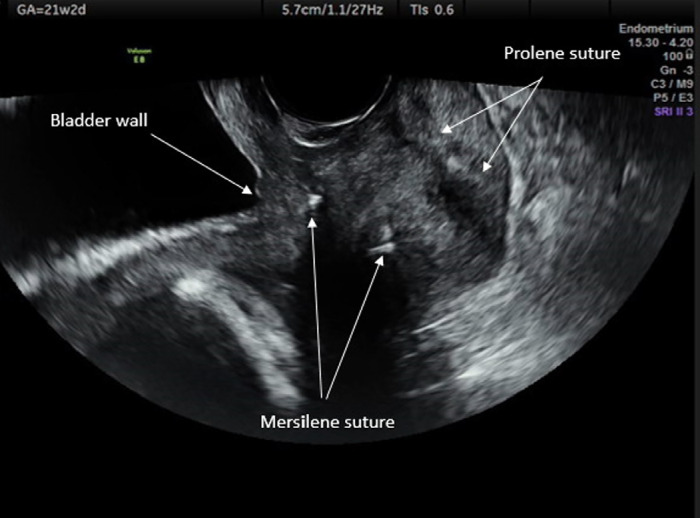

Results: EmC was performed after amnioreduction in 11 twin pregnancies. Nine patients who refused EmC were followed up with expectant management. The mean gestational age at first examination was similar between the EmC (21.36±1.62 weeks) and control group (21.00±3.16 weeks, p=0.372). The median (range) volume of removed amniotic fluid was 151.82 (120-420) mL. Cases in the EmC group gained a significantly longer delay until delivery (47.72±28.14 days) compared to controls (2.33±0.5 days, p<0.001). All of the women in the control group gave birth within three days following admission to hospital. The mean gestational age at birth was significantly higher in the EmC group (28.18±4.53 weeks) than in the control group (21.57±3.53 weeks, p<0.001). Thirteen (59.09%) infants survived in the EmC group while only two infants (22.22%) of one patient survived in the control group (p<0.001).

Conclusion: EmC increases the survival rate of infants by prolonging the gestational age at delivery in twin pregnancies. Clinicians and patients should be encouraged regarding the use of EmC in twin pregnancies with a fully dilated cervix and prolapsed amniotic membranes.